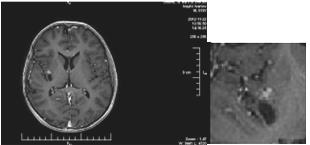

We present a 57-year-old woman with solitary intracranial plasmacytoma (SICP). Intensively modulated prophylactic wholebrain radiotherapy (WBRT) with DD 3 Gy up to TD 30 Gy / Biologically equivalent dose (BED) 38 Gy / 5 times per week was performed. The first local recurrence occured 1.5 years after the WBRT, and the second local recurrence occured 5 months after its surgical extirpation (Figure 5 & 7/A).

Figure 5: MRI - Second local recurrence of solitary intracranial plasmacytoma after prophylactic whole-brain radiotherapy.

From the studies: Bone scintigraphy, bone marrow biopsy, serum protein immunoelectrophoresis, serum levels of immunoglobulins, serum lactate dehydrogenase, calcium, albumin, renal function, beta-2 microglobulin levels - all without abnormalities. We performed local intensity-modulated radiotherapy (IMRT) by the VMAT method in the area of recurrence up to TD 45 Gy with DD 1.8 Gy / 25 fractions (Figure 6).

Due to seizure symptoms 2 weeks after RT, the irradiated relapse (Figure 7/B) was operated and histologically confirmed as necrotic brain tissue.

Brain metastases represent a significant cause of cancer morbidity, occurring in around 30% of patients with a malignancy originating outside the central nervous system [29]. The management of intracranial metastatic disease is made complicated by the impermeability of the blood-brain barrier to many chemotherapeutic agents, rendering this region a ‘sanctuary site’ for malignancies, most commonly breast, lung, melanoma, and renal cell carcinoma [30]. WBRT was the historic standard of care prior to the widespread use of radiosurgery (RS) [31]. For patients with multiple brain metastases or presenting with uncontrolled primary tumor or multiple extracerebral metastases, WBRT is the treatment of choice, associated with corticosteroids as symptomatic treatment. Fractionation schedules are varied (30 Gy in 10 fractions, 20 Gy in 4 or 5 fractions), but none has proven superiority in terms of prolonging OS [32]. Still, it has been postulated that patients with a more favorable survival prognosis could benefit from a protracted radiotherapy (RT) regimen, whereas patients with a poorer prognosis should receive shorter course RT [33]. For the statistical analysis of these heterogeneous regimens, total doses were normalized to 2 Gy and the biologically equivalent dose (BED) was calculated, with a α/β ratio of 3, for long term toxicities in brain tumors [34]. There are different opinions about the radiation toxicity on the cognitive brain function after WBRT - no changes, reported adverse effects and even initial improvement [35-40]. However, the principle concern with WBRT, particularly in patients with a more favourable prognosis, is the negative impact on neurocognitive function and quality of life [41]. WBRT in brain metastases has been associated with subacute and late neurotoxicity, causing reduced cognitive function, including reduced memory [20]. The second clinical case is an extremely rare extramedullary brain plasmocytoma (EMBP) with intracranial localization [42]. Craniocerebral solitary plasmocytom may occur from the skull (the grain or cranial base), the solid brain sheath and less frequently in the brain parenchyma [43].

There are publications for full cure after biopsy and local RT,

as solitary plasmocellular neoplasms are extremely radiosensitive

[49]. In EMBP after self-RT without surgery, increased OS has been

reported [50]. RT up to TD 50 Gy for 5 weeks on the cranial base

EMP achieves excellent healing output and local tumor control

(LTC) over 85% [51]. Optimal treatment in most patients with

EMBP is local RT up to TD 40-50 Gy with DD 1.8-2 Gy [52]. After

operating in the clinical case with EMBP, the WBRT (10 fractions

with DD 3Gy up to TD 30 - BED 38 Gy) was conducted, instead of

local radiation in the tumor bed up to TD 50Gy. This is the reason for the first recurrence, that was operated. Subsequently, after one

year, a second recurrence appears, which we irradiated locally up to

TD 45Gy (Figure 6). Although the total BED does not exceed 100Gy,

due to the extremely radiosensitiv plasmocytoma, brain tissue

necrosis develops (Figure 7/B).